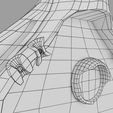

神经肌肉接头示意图